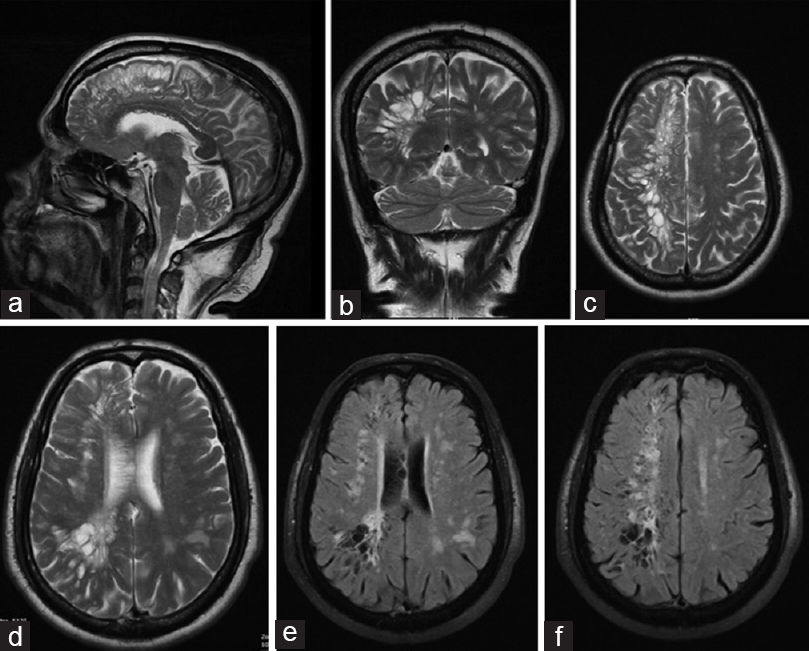

A diagnosis of limbic encephalitis was made. She was started on IVIG x 5 days. HbA1c was 6.4%. An autoimmune encephalitis panel and PET CT turn up negative. She comes for a second opinion. After admission her blood sugar is noted to be 500 mg 🍩🍩🍭